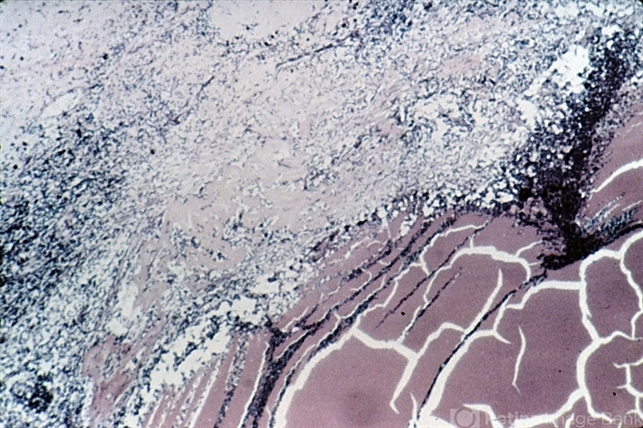

- Phacoanaphylaxis. The lens (upper left) is surrounded by an intense granulomatous inflammatory reaction. Note the ruptured lens capsule which is thrown into folds.